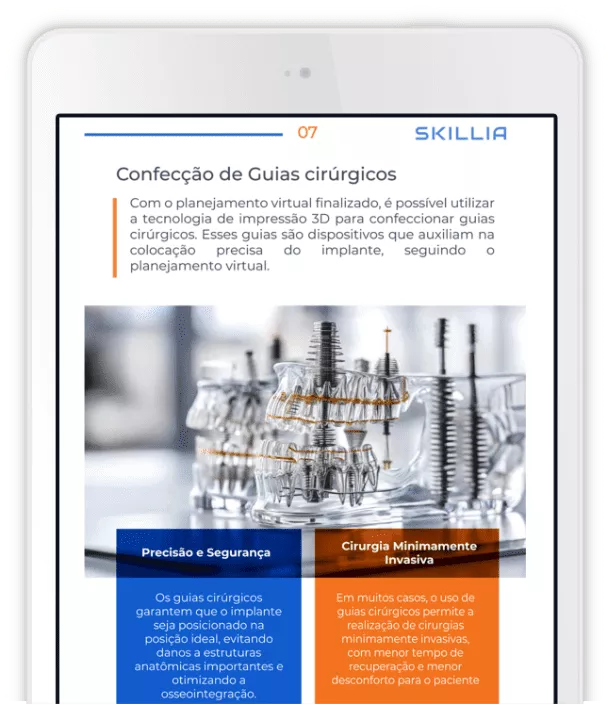

A revolução digital já chegou aos consultórios: softwares de planejamento, scanners 3D, impressão de guias cirúrgicos e inteligência artificial estão redefinindo como os implantodontistas atuam e os profissionais que não se atualizam correm o risco de ficar para trás.

Descubra no nosso e-book

como acompanhar as novas tendências da implantodontia e aplicar no seu dia a dia clínico.

Descubra como a tecnologia digital está transformando a implantodontia e elevando a precisão cirúrgica. Saiba escolher o implante certo para cada caso e levar sua prática ao próximo nível.

Da prática clínica à precisão cirúrgica.

Autor: Dr. Tiago Zanet.